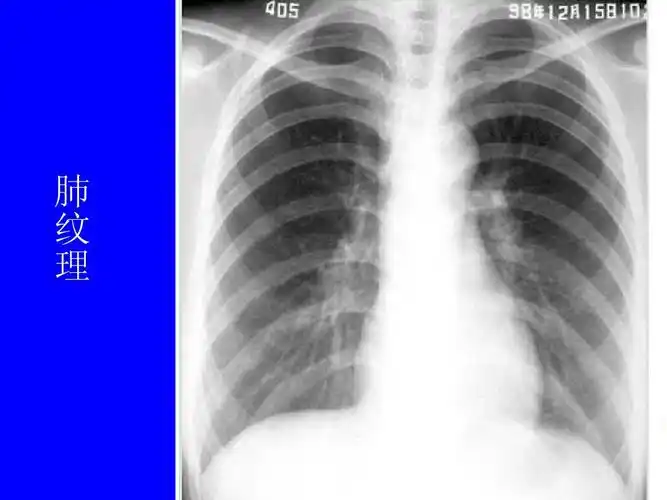

肺部正常和x线异常表现ppt